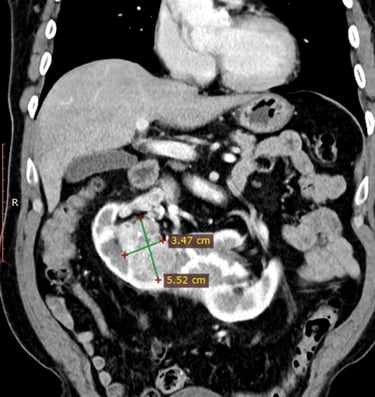

Ліва та права нирки були з’єднані перешийком висотою майже 5 см, що формувало характерну форму підкови (див. КТ-знімок).

пухлину нижнього сегмента правої половини підковоподібної нирки

пухлинний тромб у правій нирковій вені